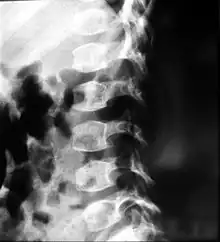

X-ray of the spine in a person with spondyloepimetaphyseal dysplasia